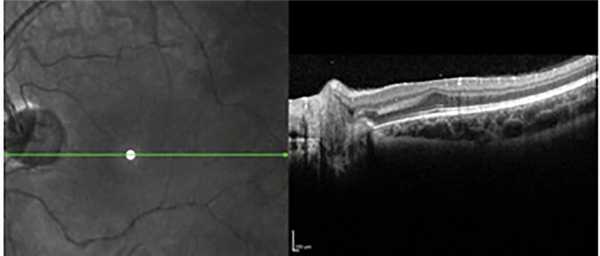

С помощью Spectralis-OCT оценивалось структурно-анатомическое состояние центральных и более периферических отделов сетчатки. Исследование проведено на 124 глазах в условиях мидриаза. В результате исследований на 23 глазах выявлена гиперрефлективная мембрана на поверхности сетчатки (эпиретинальный фиброз), на 16 глазах - уплотнение слоев стекловидного тела, прилежащего к сетчатке (преретинальный фиброз), на 12 глазах - плотные фиксированные тяжи в стекловидном теле, связанные с сетчаткой (рис. 5).

На 11 глазах с экстраретинальной тканью и преретинальным фиброзом выявлен тракционный ретиношизис, не обнаруженный при офтальмоскопии. При прицельном сканировании зон фиксации преретинальных тяжей и тракционной деформации сосудов и сетчатки в зоне папилло-макулярного пучка при III степени РН на 6 глазах выявлена локальная тракционная отслойка сетчатки, также не визуализированная при других методах исследования, что свидетельствует об информативности и прогностической значимости ОКТ [3] (рис. 6).